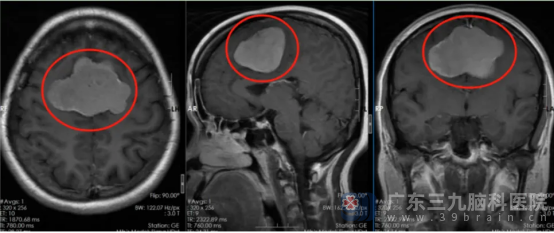

我院神经外五科学科带头人鲁明接诊患者后,根据影像资料,发现患者双侧额顶部镰旁占位性病变,大小约63mm×45mm×44mm,考虑肿瘤性病变,头颅CTA检查提示肿瘤供血极其丰富。神经外五科副主任卢建侃迅速邀请多学科专家会诊,初步判断病变可能为脑膜瘤,需尽快手术干预。

▲术前影像资料